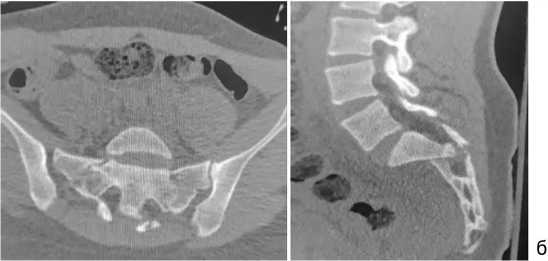

Результат более 85 баллов по шкале Majeed (международная шкала отдаленных результатов хирургического лечения нестабильных повреждений костей таза и крестца) является отличным. Мы планируем удалить металлоконструкции. На компьютерных томограммах таза через шесть (рис. 5) и 12 мес. после операции (рис. 6) определяли консолидацию переломов таза и крестца, металлоконструкции стабильны.

Рис. 6. Компьютерные томо-граммытаза, один год после операции: а — 3D-реконструкции; б — сканы во фронтальной и сагиттальной проекциях